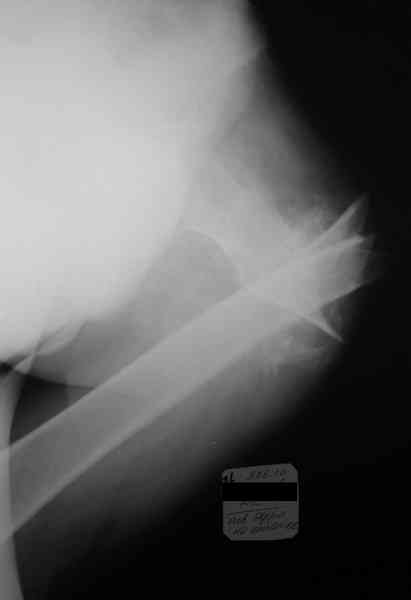

Уважаемые коллеги! Прошу помощи по приведенному случаю. Пациент 34 лет бомж получил травму окло 1,5-2 мес назад. За мед помощью не обращался. При поступлении левая нижняя конечность резко ротирована кнутри, варусная деформация бедра. По наружной поверхности рана 2 на 2 см с незначительным серозно гнойным отделяемым,умеренными грануляциями, в ране дистальный отломок бедреной кости. Патологическая подвижность в области перелома назначительная. Проведена попытка репозии дистракционным аппаратом, с незначительным эффектом (несколько уменьшилась внутренняя ротация.Что делать дальше? Остеотомия? Санация гнойного очага

Я бы начал с резекции мёртвой кости и хирургической обработки раны, поставил бы АВФ и цементные бусы с антибиотиками. После 6-ти недельного курса антибиотиков, фиксировал бы перелом штырём. Так как перелом весьма проксимальный (трудно судить по этому рентгену, надо сделать рентген с бедром на вытяжении), то есть вариант резекции прохимального отломка (Girdlestone arthroplasty). Нога укоротиться и пациент будет хромать, но будет ходить без болей. Но его можно будет мобилизировать довольно быстро, избегая проблемы с длительным постельным режимом и вытяжением. Учитывая, что больной вероятно не будет особо строго следовать указаниям врачей, это неплохой вариант для него и избежит осложнений с длительным лечением.

Произведена секвестрэктомия, остеотомия костной мозоли(кстати говоря мозоль оказалась довольно таки приличной) Рана ушита нагрухо. Наложено ДСВ за мышелки бедра. Рана зажила первичным натяжением. Пациенту наложен коксит, готовится на выписку.